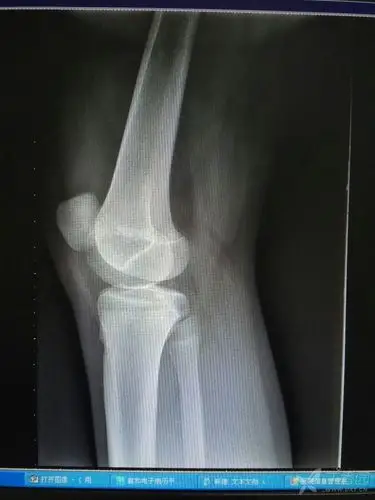

11岁女孩髌骨复发性脱位,手术治疗病例 - 好大夫在线

一例儿童髌骨脱位,讨论如何治疗 [病例帖]

先天性髌骨脱位

髌骨骨折